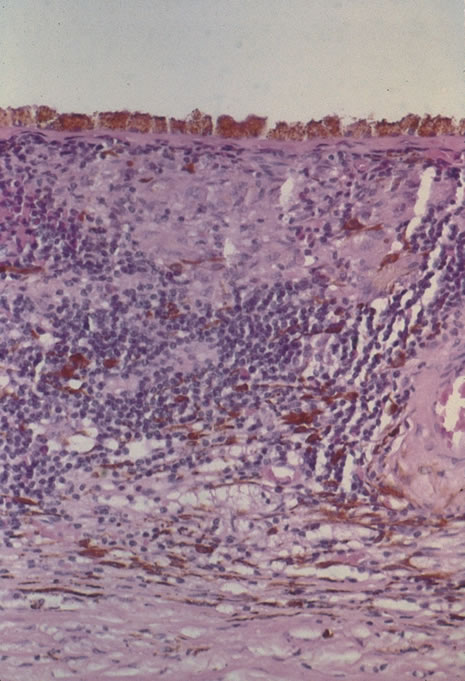

Classic histopathology consists of caseating granulomatous inflammation in a zonal distribution. The noncaseating tubercle may be present but is less specific (Fig. 18). The organism is acid-fast, meaning that it does not decolorize with acid alcohol after staining with basic fuchsin, appearing as bright red, long thin rods. A definitive laboratory diagnosis of intraocular tuberculosis may be made via anterior chamber tap, vitreous or chorioretinal biopsy depending on the site of inflammation. The PCR may be helpful in making the diagnosis.